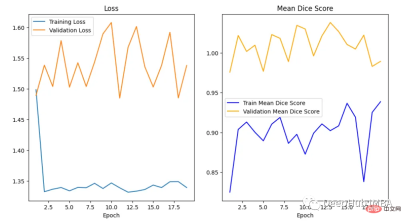

绘制损失和精度曲线

训练曲线表示模型的学习情况,验证曲线表示模型泛化到未见实例的情况。我们使用matplotlib来绘制图形。还可以使用TensorBoard,它使理解和调试深度学习程序变得更容易,并且是实时的。

在曲线中,我们可以看到模型是过拟合的,因为验证损失上升而训练损失下降。这是深度学习算法中一个常见的陷阱,其中模型最终会记住训练数据,而无法对未见过的数据进行泛化。

避免过度拟合的技巧:

- 用更多的数据进行训练:更大的数据集可以减少过拟合。

- 数据增强:如果我们不能收集更多的数据,我们可以应用数据增强来人为地增加数据集的大小。

- 添加正则化:正则化是一种限制我们的网络学习过于复杂的模型的技术,因此可能会过度拟合。

我们可以看到Dice得分曲线的行为相当不寻常。主要是因为验证平均Dice得分高于1,这是不可能的,因为这个度量是在0和1之间。我们无法确定这种行为的主要原因,但我们建议在多类问题中为每个类单独提供度量计算,并始终提供可视化示例以进行可视化评估。